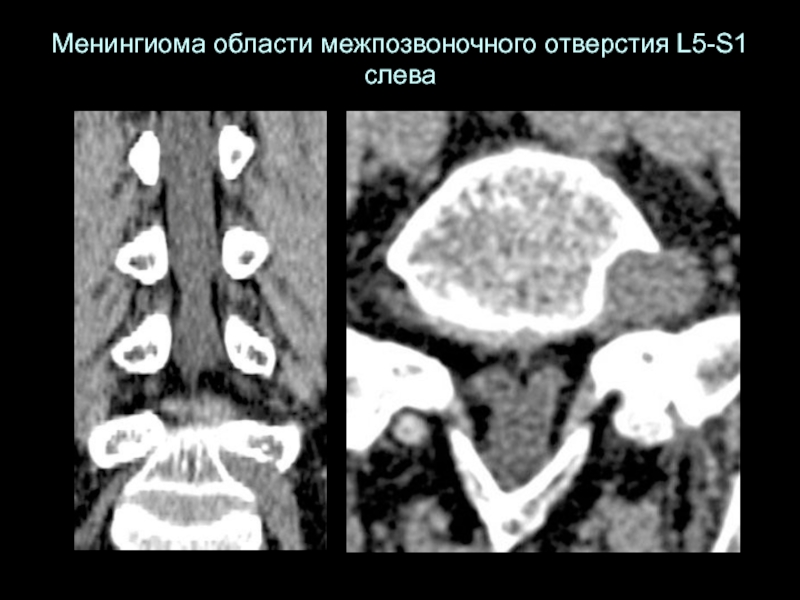

Слайд 24Менингиома области межпозвоночного отверстия L5-S1 слева

Менингиома области межпозвоночного отверстия L5-S1 слева